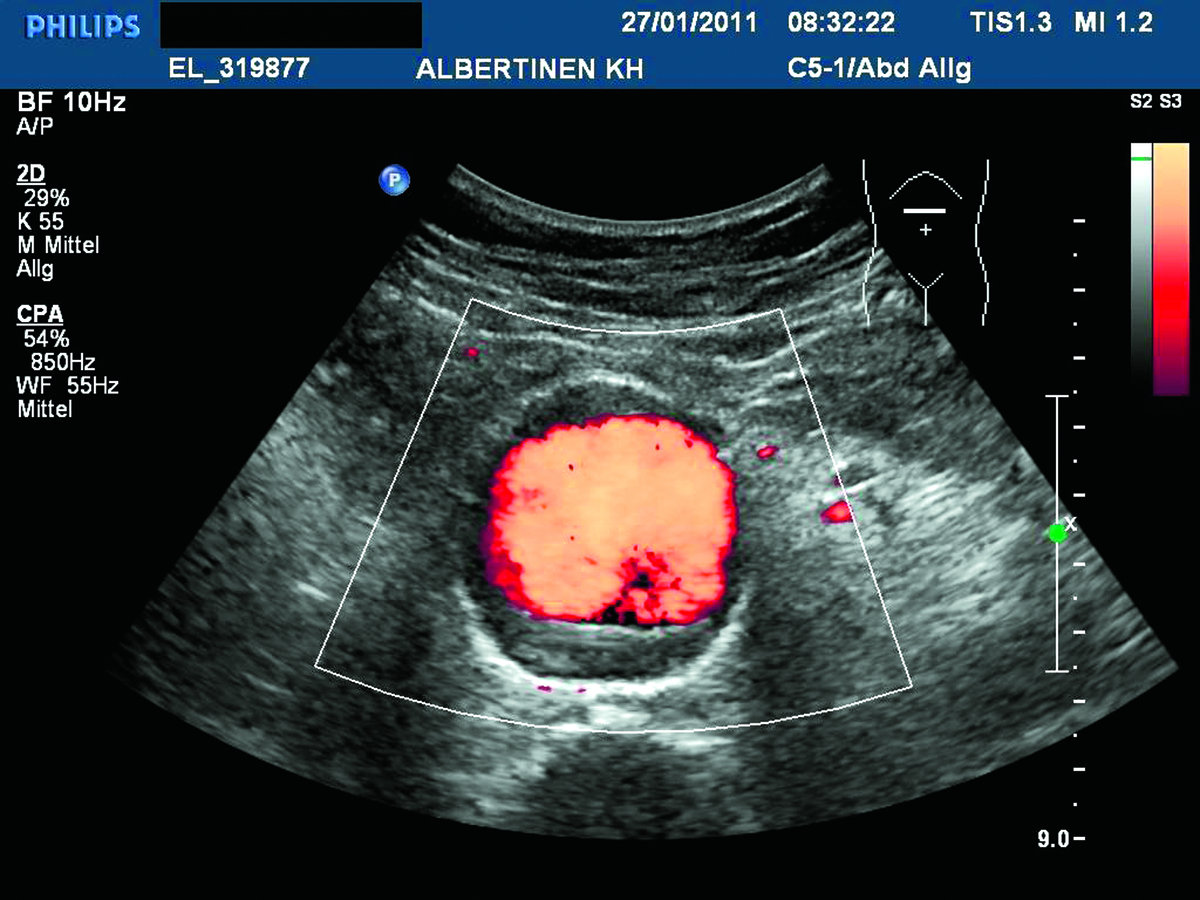

Ist der Durchmesser des Bauchaortenaneurysmas kleiner als 5,5 cm, liegt das Rupturrisiko bei max. 1,61/100 Patientenjahre. Ist der Durchmesser des Bauchaortenaneurysmas kleiner als 5,5 cm, liegt das Rupturrisiko bei max. 1,61/100 Patientenjahre. © Albertinen-Krankenhaus Hamburg, sonographiebilder.de

Sonographie eines Bauchaortenaneurysmas Sonographie eines Bauchaortenaneurysmas © Albertinen-Krankenhaus Hamburg, sonographiebilder.de